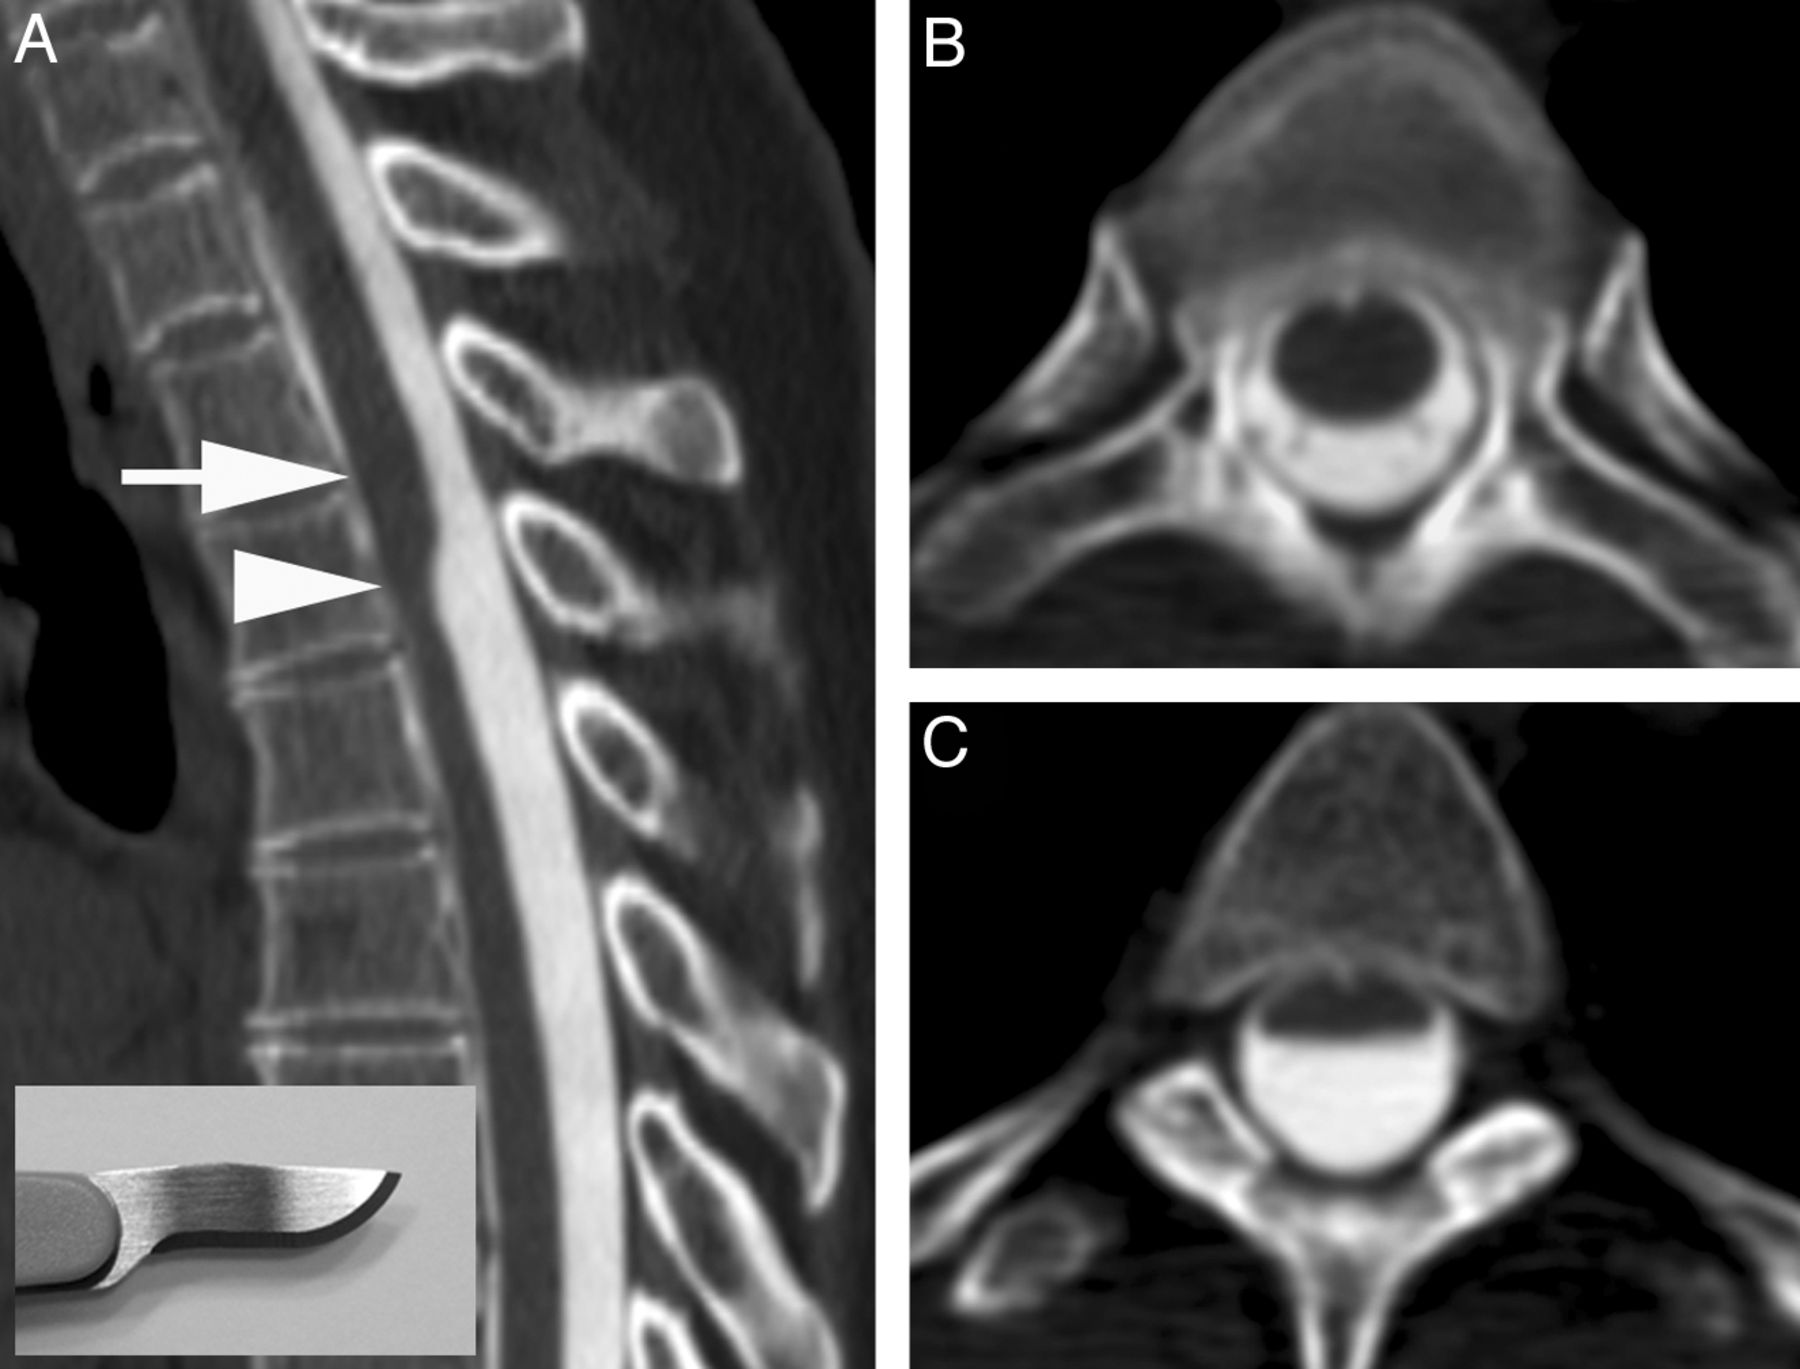

A, CT myelogram demonstrates the scalpel sign with the characteristic focal dorsal indentation of the upper thoracic spinal cord. An insert of a scalpel shows how the dorsal indentation relates to the pointed edge of the blade. B, Corresponding axial image above the level of dorsal indentation (level of the arrow in A). C, Corresponding axial image at the level of dorsal indentation (level of the arrowhead in A).

We present a series of cases that demonstrates a characteristic focal dorsal indentation of the upper thoracic spinal cord, coined the “scalpel sign” because of the resemblance on sagittal MR imaging and CT myelographic images to a scalpel with its blade pointing posteriorly (Fig 1). We propose that the presence of an arachnoid web in the dorsal subarachnoid space can result in progressive alterations of the CSF flow dynamics and eventually lead to syringomyelia. MR imaging and CT myelography currently lack the resolution to consistently identify these thin webs of tissue. However, recognition of a reliable secondary imaging finding, the scalpel sign, can suggest the presence of an arachnoid web, allowing proper neurosurgical referral and potentially curative treatment.